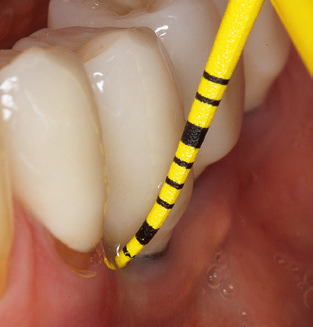

The current working concept for SPT

Updating the patient’s medical history is an important aspect of SPT and should occur at least once per year. It helps the dental team to identify and document any new risk factors. Especially when a patient is treated over many years, it is important to establish whether patient-specific and general health risk factors have changed. This primarily concerns a heightened risk as a result of diabetes, but other general conditions (cardiovascular disease and neoplasia) can also produce a modified risk profile as a result of the treatment performed and medication administered. Accordingly, updating the medical history as part of SPT is very important, as a modified risk profile may trigger the need to adapt the treatment interval. In the next step, it is important to afford the diagnostics due attention. Whilst instruments are a central aspect of SPT, findings and their documentation must never be neglected. The periodontological findings are essential for a good diagnosis; increases in the pocket depths and the BOP index are clear indicators of advancing periodontal and peri-implant disease. As such, the team should not shy away from probing implants too, with the aim of gathering the requisite data. At the same time, it is important to use periodontal probes with millimetre markings. Metallic probes have already been used for determining pocket depths around natural teeth for decades. In the case of implants, the challenge of recording correct and reproducible pockets depths is even greater. As the discrepancy between the implant diameter and the contour of the superstructure regularly results in overcontouring of the superstructure, flexible probes which still feature millimetre markings are a sensible solution for measuring pocket depths around implants (e.g., Colorvue Kit PCV11KIT6, HuFriedy; Fig. 4).